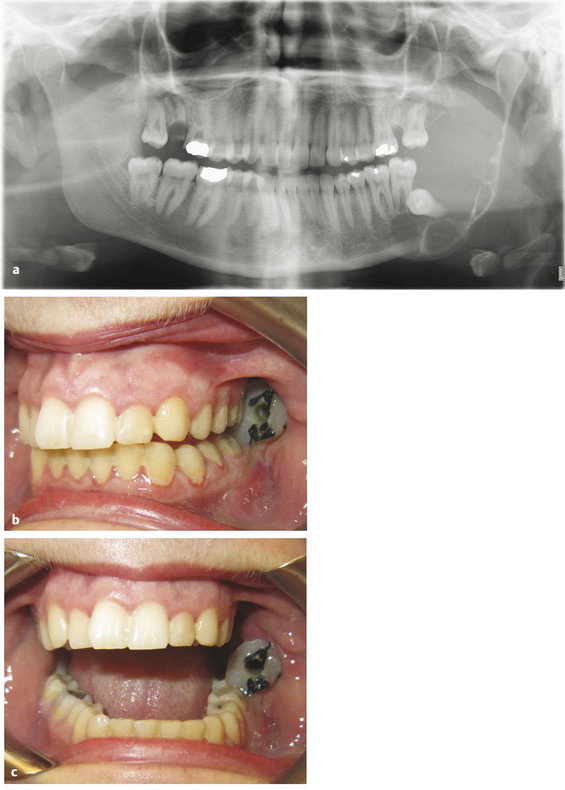

9.4.6 Ameloblastic Fibro-odontoma

Ameloblastic fibro-odontoma (AFO) is usually seen in teenagers as an asymptomatic jaw expansion that may resorb adjacent teeth. It has a mixed radiolucent–radiopaque presentation and is radiographically similar to a developing odontoma (Fig. 9‑9a). Majority of these tumors are found in the posterior mandible and are often associated with an unerupted tooth. Treatment includes simple enucleation and curettage (Fig. 9‑9b, c). Prognosis is excellent, and recurrence is rare.